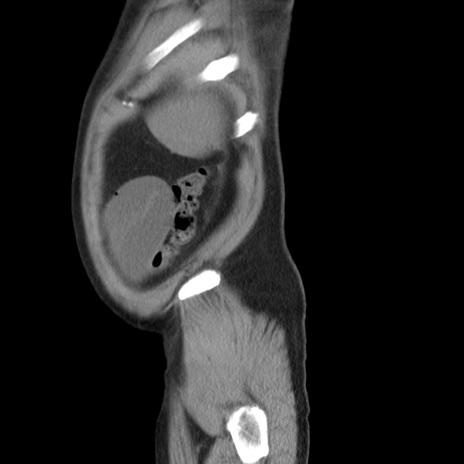

横断像

【症例】 60歳代男性

【主訴】 腹部膨満、嘔吐

【現病歴】5日前頃より倦怠感を認め食事量減少し4日前の朝嘔吐、食事摂取困難となった。 3日前近医受診し点滴施行され整腸剤などを処方された。 当日他院を受診し、腹部膨満著明、炎症反応の上昇(CRP10.8、WBC11200)あり、紹介受診となる。

【身体所見】 意識JCS1 受け答えがはっきりしないBP 111/57mHg、 P 67bpm、、BT35.2°C、SpO2 97%(RA)、 腹部:膨隆、打診で鼓音あり、全体的に圧痛有り、腸蠕動音(-)、反跳痛ははっきりせず。

【データ】WBC 11400、CRP 14.20